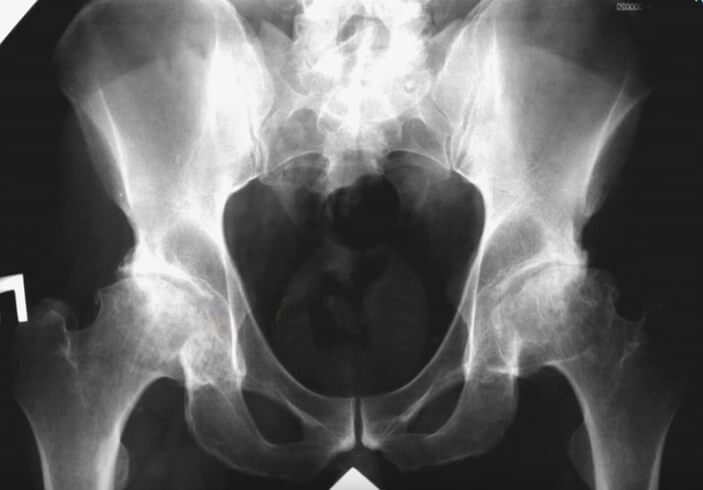

Асептические некрозы головок бедренных костей с последующим развитием всех признаков ОА (на фото рентгенограмма пациентка с системной красной волчанкой, которая длительное время лечится глюкокортикоидами